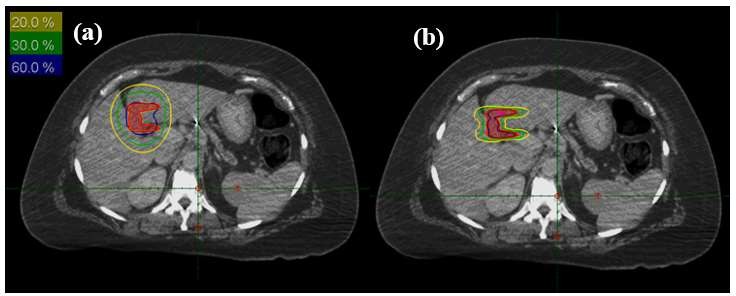

For our first target drawn on a patient CT, a plan was generated using RT Pro TPS optimization as shown in Fig. 5. The number of shots was limited to 3 during the optimization. The resulting plan showed 97% coverage and a 1.28 conformity index. We reran the optimization after increasing the shot numbers to 5 shots. The resulting plan showed better conformity being on the order of 1.09 with a slight reduction in coverage being on the order of 95.7%. On the other hand, using modulated arc sectors with only one shot, a plan was generated with 1.03 CI and 99% coverage. Thus, one shot with weighted sectors can achieve the same coverage/conformity index as that obtained with multiple shots. This also resulted in a considerable reduction in delivery time by 55%. Our second studied target was a C shaped target. A plan was generated using regular shots and, as can be seen in Fig. 6.a, it is challenging to contour the isodose lines around this irregularly shaped target. Subsequently, another plan was created using modulated shot delivery having a combination of full and partial arcs. Figure 6.b shows better conformal isodose distribution with the use of this approach.

Figure 6: RGS plans using regular shots as compared to modulated shots a) Isodose distribution for a plan using regular shots, b) Isodose distribution for a plan using modulated shots.